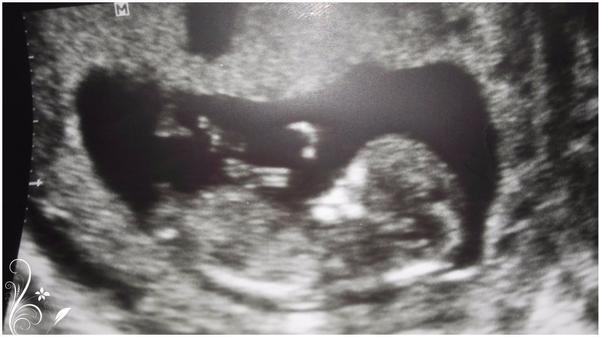

Devcata a co byste rekli me fotce? Na str.33. Dekuji.

Ze 60% holcicka.. Ze 40% vidim pytlik s kulkama..